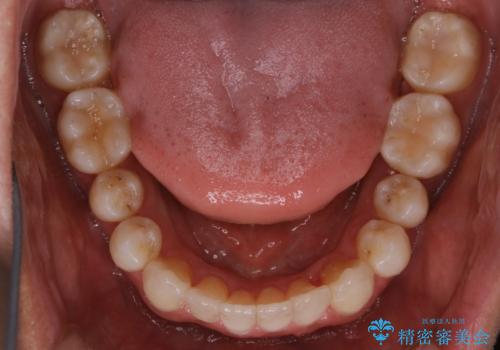

【非抜歯】八重歯を治す マウスピース矯正

- 前歯のガタつきの治療を主訴にご来院されました。

目立たない装置をとのご要望があったため、検査結果をふまえてインビザラインでの非抜歯矯正を行うこととなりました。

非抜歯での治療

抜歯をせずに歯のガタつきを治すためのスペースを作るために

①歯の遠心移動

②歯列弓の拡大

③IPR(歯を少し小さく削る)

この3つの方法を複合的に組み合わせて治療を行いました。